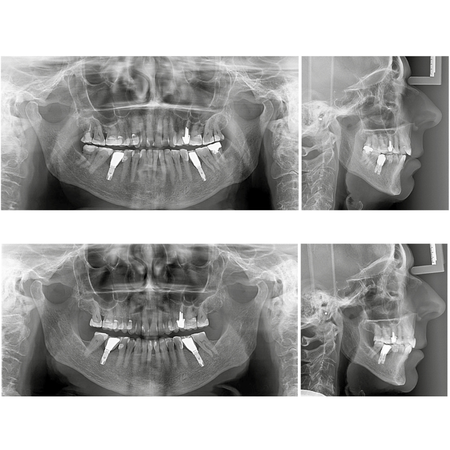

Orthodontic-rehabilitative treatment of Class II malocclusion and anterior open bite in a patient with implants in the lower first molar region: case report treated with aligners

INTRODUCTION: Orthodontic aligners have emerged as an alternative to fixed appliances, particularly for adult patients seeking greater comfort and improved esthetics. OBJECTIVE: This clinical case report describes a 72-yearold female patient who sought orthodontic treatment due to esthetic and functional complaints related to an anterior open bite and a Class II malocclusion, absence of tooth #31, and painful symptoms in the condylar regions. Treatment included an orthodontic phase using...